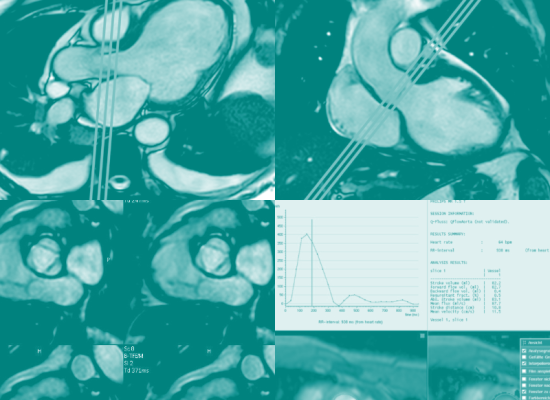

008 Aortenklappe und

Flussmessung